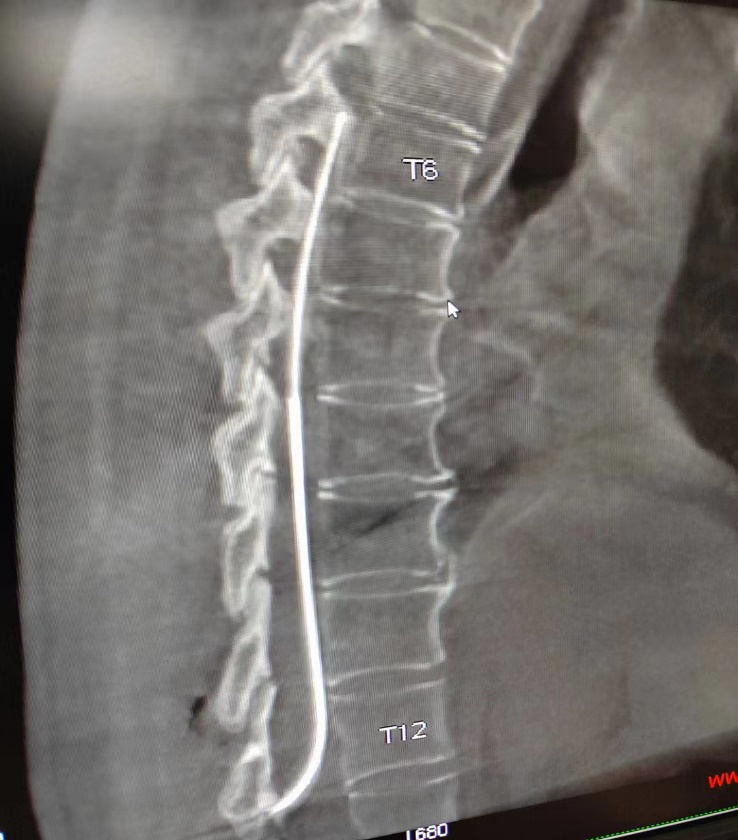

在临床医学、影像科,手术室等多学科共同参与配合下,由路桂军医师团队为患者顺利的完成了鞘内镇痛泵植入术(图1)

鞘内镇痛泵植入术用药量为静脉用药的1/100,口服药量的1/300,可降低药物的副作用,可根据病人疼痛程度调节给药剂量,同时可以通过体外“遥控器”针对爆发痛随时处理。

全植入镇痛泵,最长可维持180天更换一次药物,因镇痛导管和止痛泵均完全埋置于皮下,体内止痛泵可持续给药。